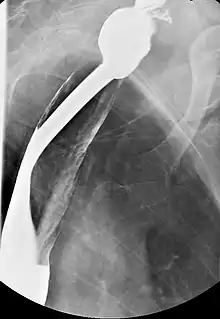

Barium esophagography and videofluoroscopy will help to detect esophageal webs. Esophagogastroduodenoscopy will enable visual confirmation of esophageal webs. The webs occur due to sub-epithelial fibrosis.

Right posterior oblique prone single contrast fluoroscopic last image hold image showing circumferential thin cervical esophageal web.